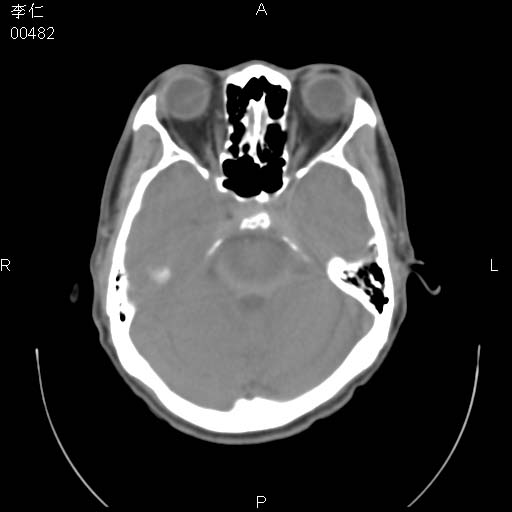

患者男,45岁。于二月前发现左眼稍肿,去看眼科,查肾功(—),来查ct,我看到的是左侧上眼睑内低密度影,ct值是-600到-700hu。

是一个副鼻窦的正常变异,脂肪瘤的密度不可能这么低,-600到-700.

只是空气而已,属正常ct表现。

正常表现,眼睑与结膜zhi间的空气

正常,为结膜囊内气体。

左侧眼球壁光滑,未见异常密度灶,眶内结构清晰,眼内肌、视神经均正常。所见低密度灶,本人考虑:1、五官科翻上睑造成;2、炎症(产气细菌感染)。